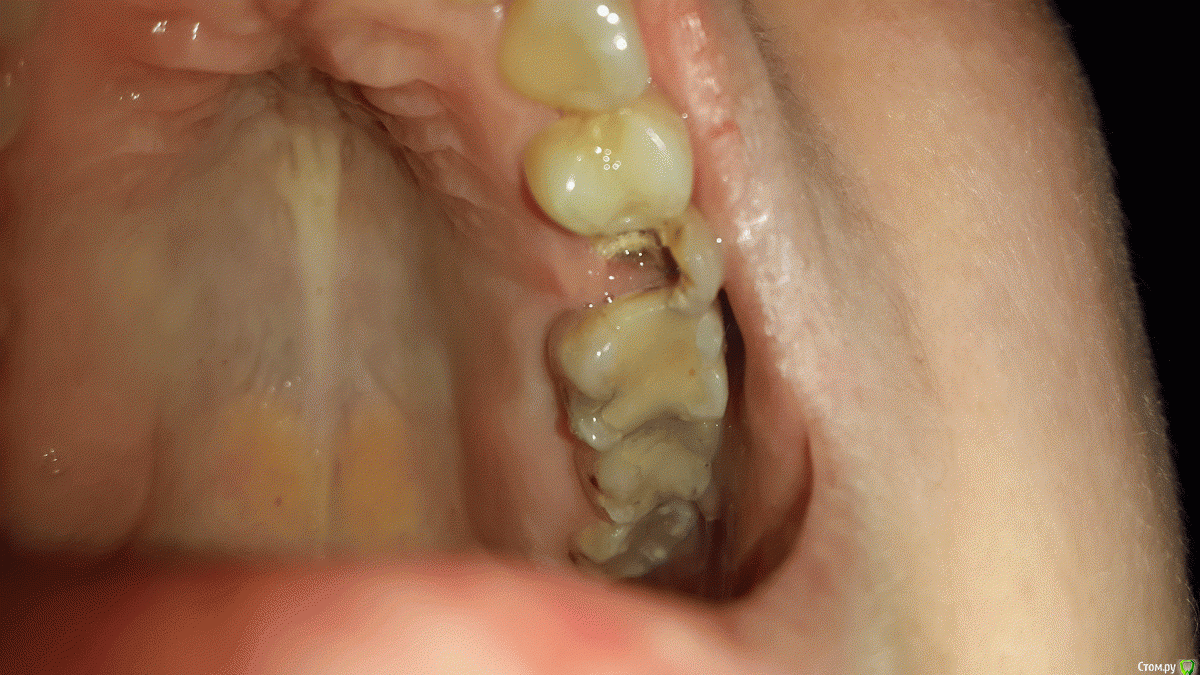

Gvozdika Опубликовано 11 февраля, 2016 Поделиться Опубликовано 11 февраля, 2016 Здравствуйте. Помогите пожалуйста принять решение: стоит ли пытаться спасать 25 зуб?История банальная: Давно стояла пломба практически во весь зуб (есть ортопантограмма как было до, сделанной год назад). Месяц назад где-то отвалилась язычная стенка под десну, еще через 2 недели - сама огромная пломба. На данный момент осталась только тонкая внешняя стенка. По результатам посещения нескольких специалистов имею 2 варианта действий:1. Культевая вкладка + коронка+перелечивание каналов (или можно обойтись без перелечивания?). Результат 50/50 и сколько эта конструкция может простоять сложно сказать.2. Смирится с потерей зуба и как следствие - имплант.Как Вы считаете? Стоит ли тратить время и деньги на первый вариант? Фото прилагаю.Спасибо за внимание. Ссылка на комментарий

___49___ Опубликовано 12 февраля, 2016 Поделиться Опубликовано 12 февраля, 2016 (изменено) скажем не "залепить " ,а "одеть остатки зубов в элегантный бронежилет ;)". ход мыслей верный. Чем меньше зубов во рту , тем чаще раскалываются оставшиеся от перегрузки, начав сейчас вы потратите меньше чем если начнете через полгода, а потратили бы еще меньше начав 1.5 месяца назад. Что касается оставить 25ый или удалить , я бы вам ответил на этот вопрос только после откидывания десны (дабы видеть уровень скола, наличие трещин) и подготовки корня под штифт...соответственно вывод напрашивается сам - идем к специалисту с желанием восстановить (при помощи культивой вкладки например) , но четко осознаем, что если во время работы доктор говорит что шансов увы нет - без какого либо сожаления удаляем (тем более вы уже готовы к этому психологически). Всегда лучше знать что ты приложил максимум усилий для того что бы спасти зуб и у тебя этого не вышло, нежели не попытавшись удалить и потом жалеть с мыслями - "а вдруг все таки можно было и спасти".п\с - качество рентген снимка (или фото) не очень. Изменено 12 февраля, 2016 пользователем ___49___ Ссылка на комментарий